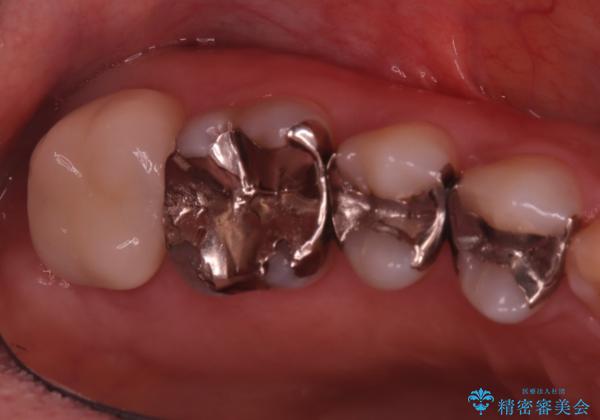

- 主訴:詰め物と歯の境目に穴が空いているとクリーニング時衛生士から指摘された。

保険適用のメタルインレー歯質の境目が虫歯になっていたため、一度メタルインレーを除去し虫歯の範囲の把握と補綴物のやり替えをお勧めし、ジルコニアクラウンでのやり替えとなりました。

保険適用のメタルインレーと歯質の境目にう窩ができており、補綴物のやり替えとなりなした。